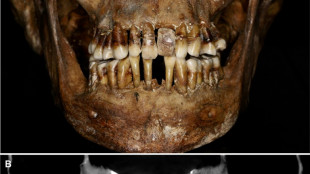

La dentition d'une aristocrate du XVIIe siècle comme marqueur social

La dépouille n'avait pas tout dit: trente ans après sa découverte, le squelette d'une aristocrate protestante du temps des guerres de religion en France vient de révéler les secrets intimes de cette personnalité controversée, qui souffrait d'une maladie bucco-dentaire fort mal soignée.